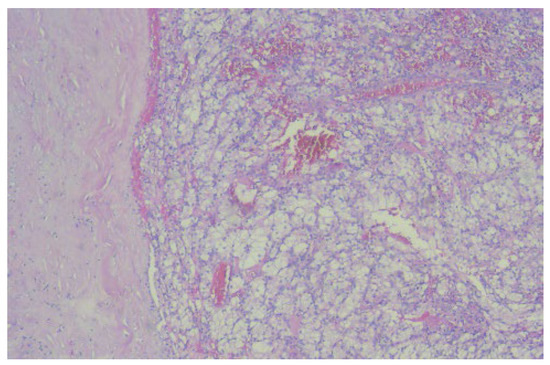

2. Case Report